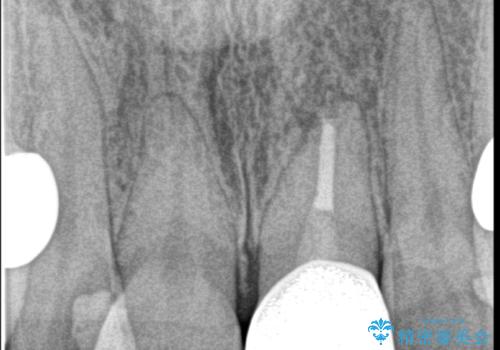

- 自転車で転倒してしまい、前歯を折ってしまい、痛みと見た目の改善を希望され来院されました。

もともと根管治療の為されて歯が折れてしまっているので、根管治療を行い審美的なセラミック治療を行う治療計画としました。

- 15.4万円(ジルコニアクラウン・仮歯・ファイバーコア)費用は治療当時の料金となります